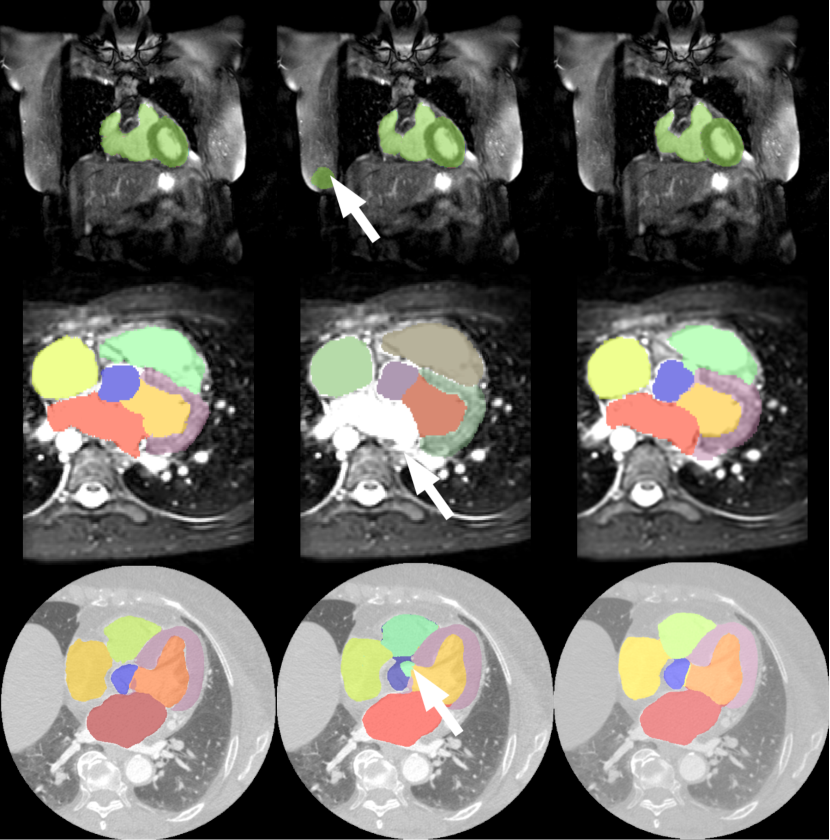

Examples of viusalized segmentation reulsts are shown in Fig. 2. Omitting the foreground localization step in the first training step may lead to misclassification of the background voxels, as shown in the top row of Fig. 2. The middle row shows that without the coarse segmentation (second step) the model failed to label left atrium, and produced inhomogeneious segmentation for aorta when skipping the joint training of Net1𝑁𝑒𝑡1Net1 and Net2𝑁𝑒𝑡2Net2 (step three).

Figure 2: Visualization of segmentation results overlapped with the original data: Ground-truth segmentations are shown on the left; the middle column shows the results obtained by omitting the first, second and third training step (from top to bottom); on the right is the results obtained with the proposed training process.